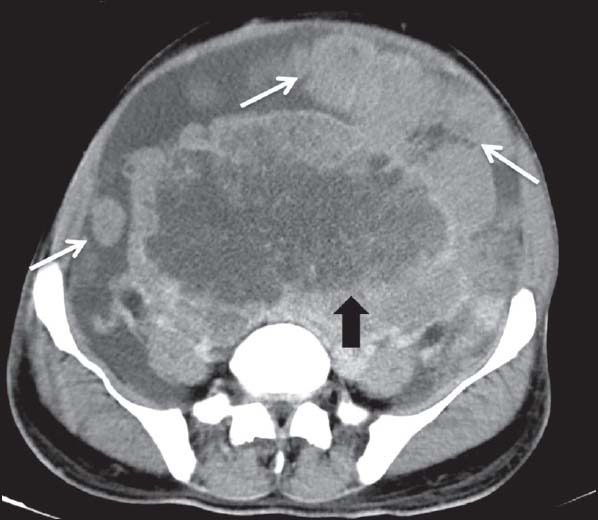

| Figure 3:Duodenal gastrointestinal stromal tumors in a 45-year-old male — (a) barium meal follow through spot image showing widening of C-loop of duodenum with mucosal irregularity (arrowhead) and ulcerations (b) coronal contrast-enhanced computed tomography image showing heterogeneously enhancing mass lesion in second part of duodenum (white arrowhead) having intraluminal as well as subserosal component without proximal obstruction

| Figure 3:Duodenal gastrointestinal stromal tumors in a 45-year-old male — (a) barium meal follow through spot image showing widening of C-loop of duodenum with mucosal irregularity (arrowhead) and ulcerations (b) coronal contrast-enhanced computed tomography image showing heterogeneously enhancing mass lesion in second part of duodenum (white arrowhead) having intraluminal as well as subserosal component without proximal obstruction